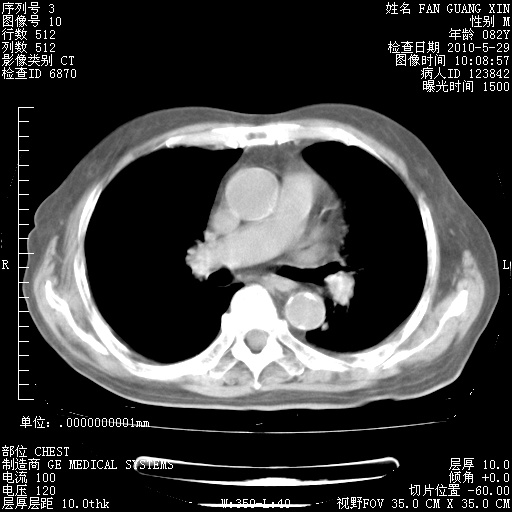

再治疗10天后的肺部CT 纵膈窗

阅读此次胸部CT,肺间质渗出性改变较入院时有吸收。目前从体温、白细胞、中性分叶明显增高,肯定存在细菌感染(发生医院感染哦,若无消化道及泌尿系统等感染的依据,肺部感染可能大)。若你院头孢哌酮舒巴坦钠耐药率较高,同意你的方案,若48小时体温仍高,可考虑使用碳青霉稀类抗菌药物,同时可予超声雾化、注意滴数时加大液体量。白蛋白33.30g/L较低哦,需加强营养等支持治疗。

从白细胞总数和中性比例看好像合并感染。肺部纹理好像比上次多,支气管炎?其他感染?